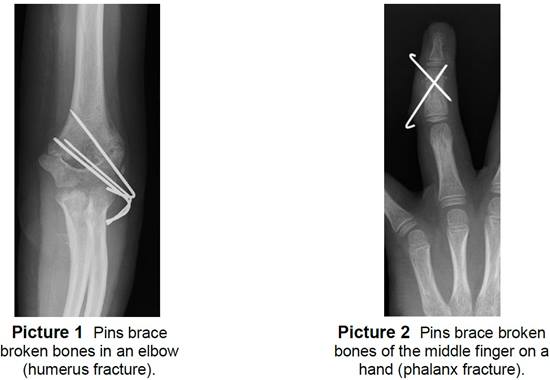

Percutaneous in medicine means that something is pushed through the skin instead of cutting the skin open like in other surgeries. With percutaneous pinning, an orthopedic surgeon (bone doctor) pushes a metal pin or wire through the skin and into the bone. One end of the pin sticks out of the skin while the other stays in the bone (Pictures 1 and 2).

- This technique holds a broken bone (fracture) together and keeps it still until it heals.